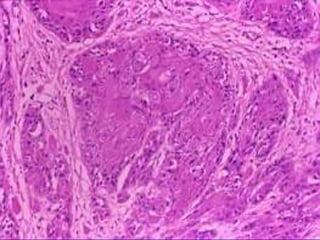

Carcinoma epidermoide

 Cáncer más común de

cavidad oral

 Adultos y viejos

 Predominio en hombres

 Labio, lengua, piso de boca,

mucosa bucal, encía inf,

sup, paladar duro

 Niños: Lengua

 Frecuentemente

multicéntricos

 Asociación a displasia, p53

 Proclividad a 2o. primarios

Carcinoma epidermoide de cavidad oral